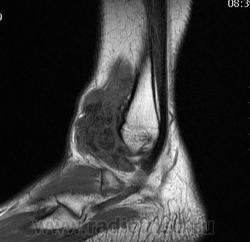

Пигментный виллёзонодулярный синовит - редкое заболевание с доброкачественным течением, характеризующееся пролиферативными изменениями синовиальной оболочки, отложением гемосидерина, образованием ворсинок, паннуса. Две разновидности: виллёзонодулярный бурсит и виллёзонодулярный тендосиновит. Частота - 2 на I 000 000. Преобладающий возраст • Виллёзонодулярный бурсит - 30-40 лет • Виллёзонодулярный тендосиновит -50-60 лет. Преобладающий пол - женский. Этиология. В 30% случаев развитию синовита предшествует травма сустава. Патоморфология. Пролиферация клеток синовиальных оболочек с образованием узлов, содержащих клеточный инфильтрат из фибробластов, лимфоцитов, макрофагов с жировыми включениями. Клиническая картина • Виллёзонодулярный бурсит -моноартрит. Чаще всего (80% случаев) поражается коленный сустав, реже - (с убывающей частотой) тазобедренный, голеностопный и плечевой суставы • Виллёзонодулярный тендосиновит - образование узелков в мышечных сухожилиях и связках сустава. Лабораторные исследования • Увеличение СОЭ • Синовиальная жидкость ксантохромная, с примесью крови • Биопсия синовиальной оболочки: узловая пролиферация, гемосидероз, инфильтрация мононуклеарными клетками. Рентгенологическое исследование • Остеопороз и наличие остеофитов нехарактерны • Артропневмография: множественные округлые дефекты наполнения синовиальной полости, обусловленные наличием узлов или гипертрофированных ворсинок синовиальной оболочки • МРТ - выявление гемосидерина и жировых включений. Артроскопия • Суставной хрящ приобретает коричневую окраску вследствие гемосидероза • Различной величины узлы коричневого цвета. Дифференциальный диагноз • Виллёзонодулярный бурсит • Липома - в аспиратах отсутствует ксантохромная жидкость • Остеоартроз - кисты возникают только на суставных поверхностях, подвергающихся нагрузке, тогда как при пигментном виллёзонодулярном синовите они образуются на всех суставных поверхностях. Остеофи-ты, напротив, более типичны для остеоартроза • Воспалительные арт-ропатии, дебютирующие моноартритом, - ревматоидный артрит, туберкулёзный артрит, анкилозирующий спондилоартрит и др. • Виллёзонодулярный тендосиновит - панглии (околосухожильные кисты): аспираты ганглиев содержат гелеподобную жидкость. Лечение хирургическое • Виллёзонодулярный бурсит • Тотальное иссечение синовиальной оболочки, вероятность рецидива заболевания составляет 25-40% • Лучевая терапия • Виллёзонодулярный тендосиновит - иссечение кист. Синоним. Синовит геморрагический МКБ. М12.2 Ворсинчато-узелковый (виллонодулярный) синовит (пигментный)

Пигментированный ворсинчато-узловой синовит (ПВУС) - пролиферативно-диспластическое поражение синовиальных оболочек суставов, слизистых сумок и сухожильных влагалищ. Обычно поражаются крупные суставы, особенно коленный. Синонимы: пигментированный ворсинчато-узловой синовит, пигментный вилонодулярный синовит, миелоксантома, гигантоклеточный синовит, фиброзная синовиальная ксантома, полиморфно-клеточная опухоль синовиальных оболочек, гигантоклеточная доброкачественная опухоль синовиального влагалища. Имеются данные, позволяющие предполагать связь заболевания с местным нарушением липидного обмена.

Рентгенологическая картина при поражении коленного сустава достаточно характерна. При поражении других суставов, что встречается значительно реже, она менее характерна, и чтобы поставить диагноз, нужно помнить о симптомах, свойственных этому заболеванию.

Основным симптомом является то, что синовиальная оболочка хорошо контрастируется на простых рентгенограммах. Это объясняется тем, что патологически разрастающаяся синовиальная оболочка богато снабжена сосудами 4-5-го порядка и капиллярами; следовательно, ее кровенаполнение резко повышено и она хорошо контрастируется. Хорошо виден резко увеличенный верхний заворот в виде белесого пятна овальной формы, иногда достигающего средней трети бедра. Поскольку его переднезадний диаметр составляет 5-7 см, увеличивается и вся масса мягких тканей.